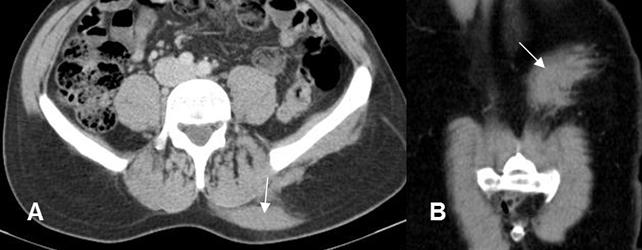

Fig 209 A. Hematoma muscular.

A: TAC axial y B: TAC reconstrucción coronal. Imagen ovalada y densa, por detrás de los músculos paravertebrales en el lado izquierdo, que aparece después de un trauma y corresponde a hematoma de tejidos blandos.